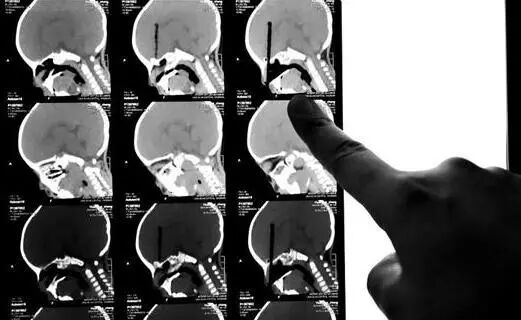

几周前,宁波一名6岁女童手拿筷子爬楼梯时不慎摔倒,大半根筷子顺着眼眶插入脑内!家人紧急送往医院,后经医生全力抢救,才保住性命。

接诊的石医生说:那天孩子送来的时候,筷子只在眼眶外露着小半截,现在想起来仍心有余悸!